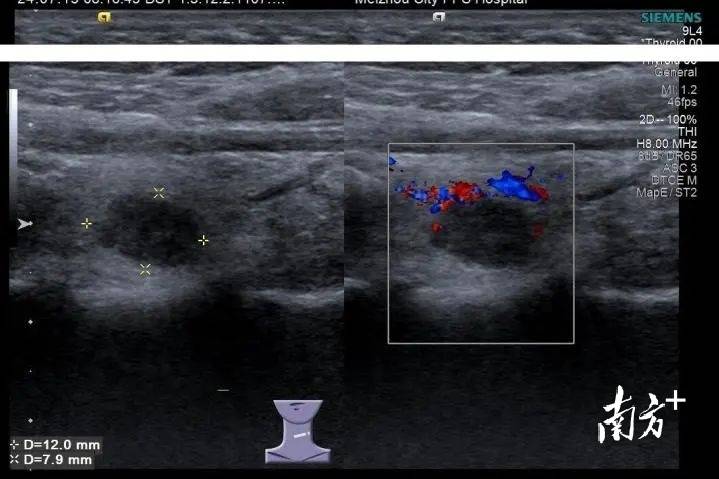

小罗是一名在校女大学生,家住在吉林省白城市,近期体检中发现甲状腺有个结节,彩超提示为C-TIRADS 4A类,存在恶性病变风险。看到检查报告时,小罗很害怕,“存在恶性病变风险”到底严不严重,要不要及时处理?

梅州市人民医院甲状腺外科副主任王悦冬在详细了解小罗病情后,建议小罗先行超声引导下甲状腺细针穿刺活检术,以明确结节性质,术后病理诊断为甲状腺乳头状癌,为恶性结节,有必要手术切除。